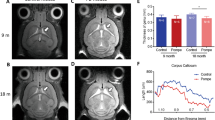

Comparison of FA and MD values of younger (age range 19.7–26.5 years) and older (age range 43.3–55.5 years) adult patients for the three white matter tracts showed values in the same range; as shown for SLF, (median FA value 0.49 (range 0.46–0.55) for the younger patients against 0.48 (range 0.43–0.54) for the older group; median MD (10–3 mm2/s) value 0.77 (range 0.72–0.79) against 0.75 (range 0.70–0.80)); the ILF, (median FA 0.53 (range 0.51–0.56) against 0.51 (range 0.46–0.55); median MD (10–3 mm2/s) 0.84 (range 0.82–0.86) against 0.83 (range 0.78–0.87)); and IFO (median FA 0.58 (range 0.54–0.59) against 0.54 (range 0.50–0.59); median MD (10–3 mm2/s) 0.82 (0.80–0.85) against 0.81 (0.77–0.85)) (Fig. 3). This is a similar pattern as to what is found in literature during adulthood (29).

Tractography in late-onset and classic infantile Pompe patients. Green: late-onset Pompe patients; red: classic infantile Pompe patients; red with blue dot: classic infantile Pompe patient without abnormalities on structural MRI; green boxplot: reference sample. FA fractional anisotropy; MD mean diffusivity, SLF superior longitudinal fasciculus, ILF inferior longitudinal fasciculus, IFO inferior fronto-occipital fasciculus